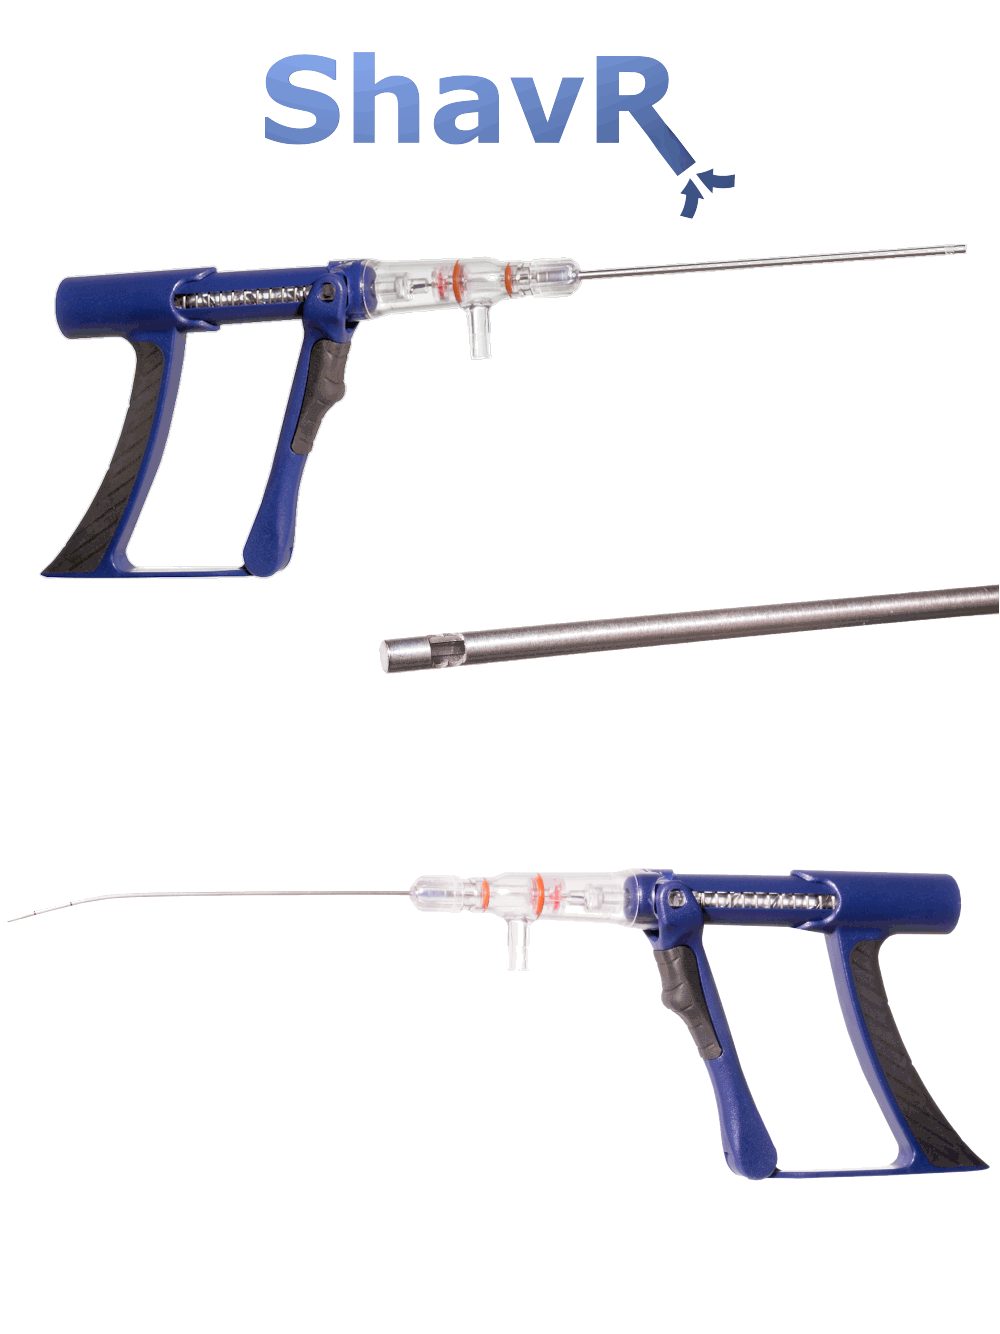

SHAVR

Tissue and/or pathology resection may be performed with a variety of surgical instruments, systems, and techniques including basic manual devices and electromechanical systems.

Basic manual devices are cost-effective and easy-to-use, but often lack speed, power, control, and effectiveness. Electromechanical systems may improve speed and power for certain cases, but require costly capital equipment, service contracts, complex set-up, and expensive disposables. Some electromechanical systems reduce physician tactile “feel” for the procedure and may introduce new risks that outweigh their benefit.

The SHAVR is a single-use, non-powered, hand-held, and hand-manipulated tool designed to combine the benefits of basic manual devices and electromechanically powered systems.

Clinicians squeeze and release the handle with their fingers to actuate cutting speed and control. Aspiration may be provided by wall suction and/or an aspiration pump. Improved control means physicians can perform surgical resection based on what they see and feel during the procedure.

INDICATIONS FOR USE: The Shavr is a non-powered, hand-held, and hand-manipulated manual surgical instrument for tissue resection. Shavr devices are “tools” not “treatments.”